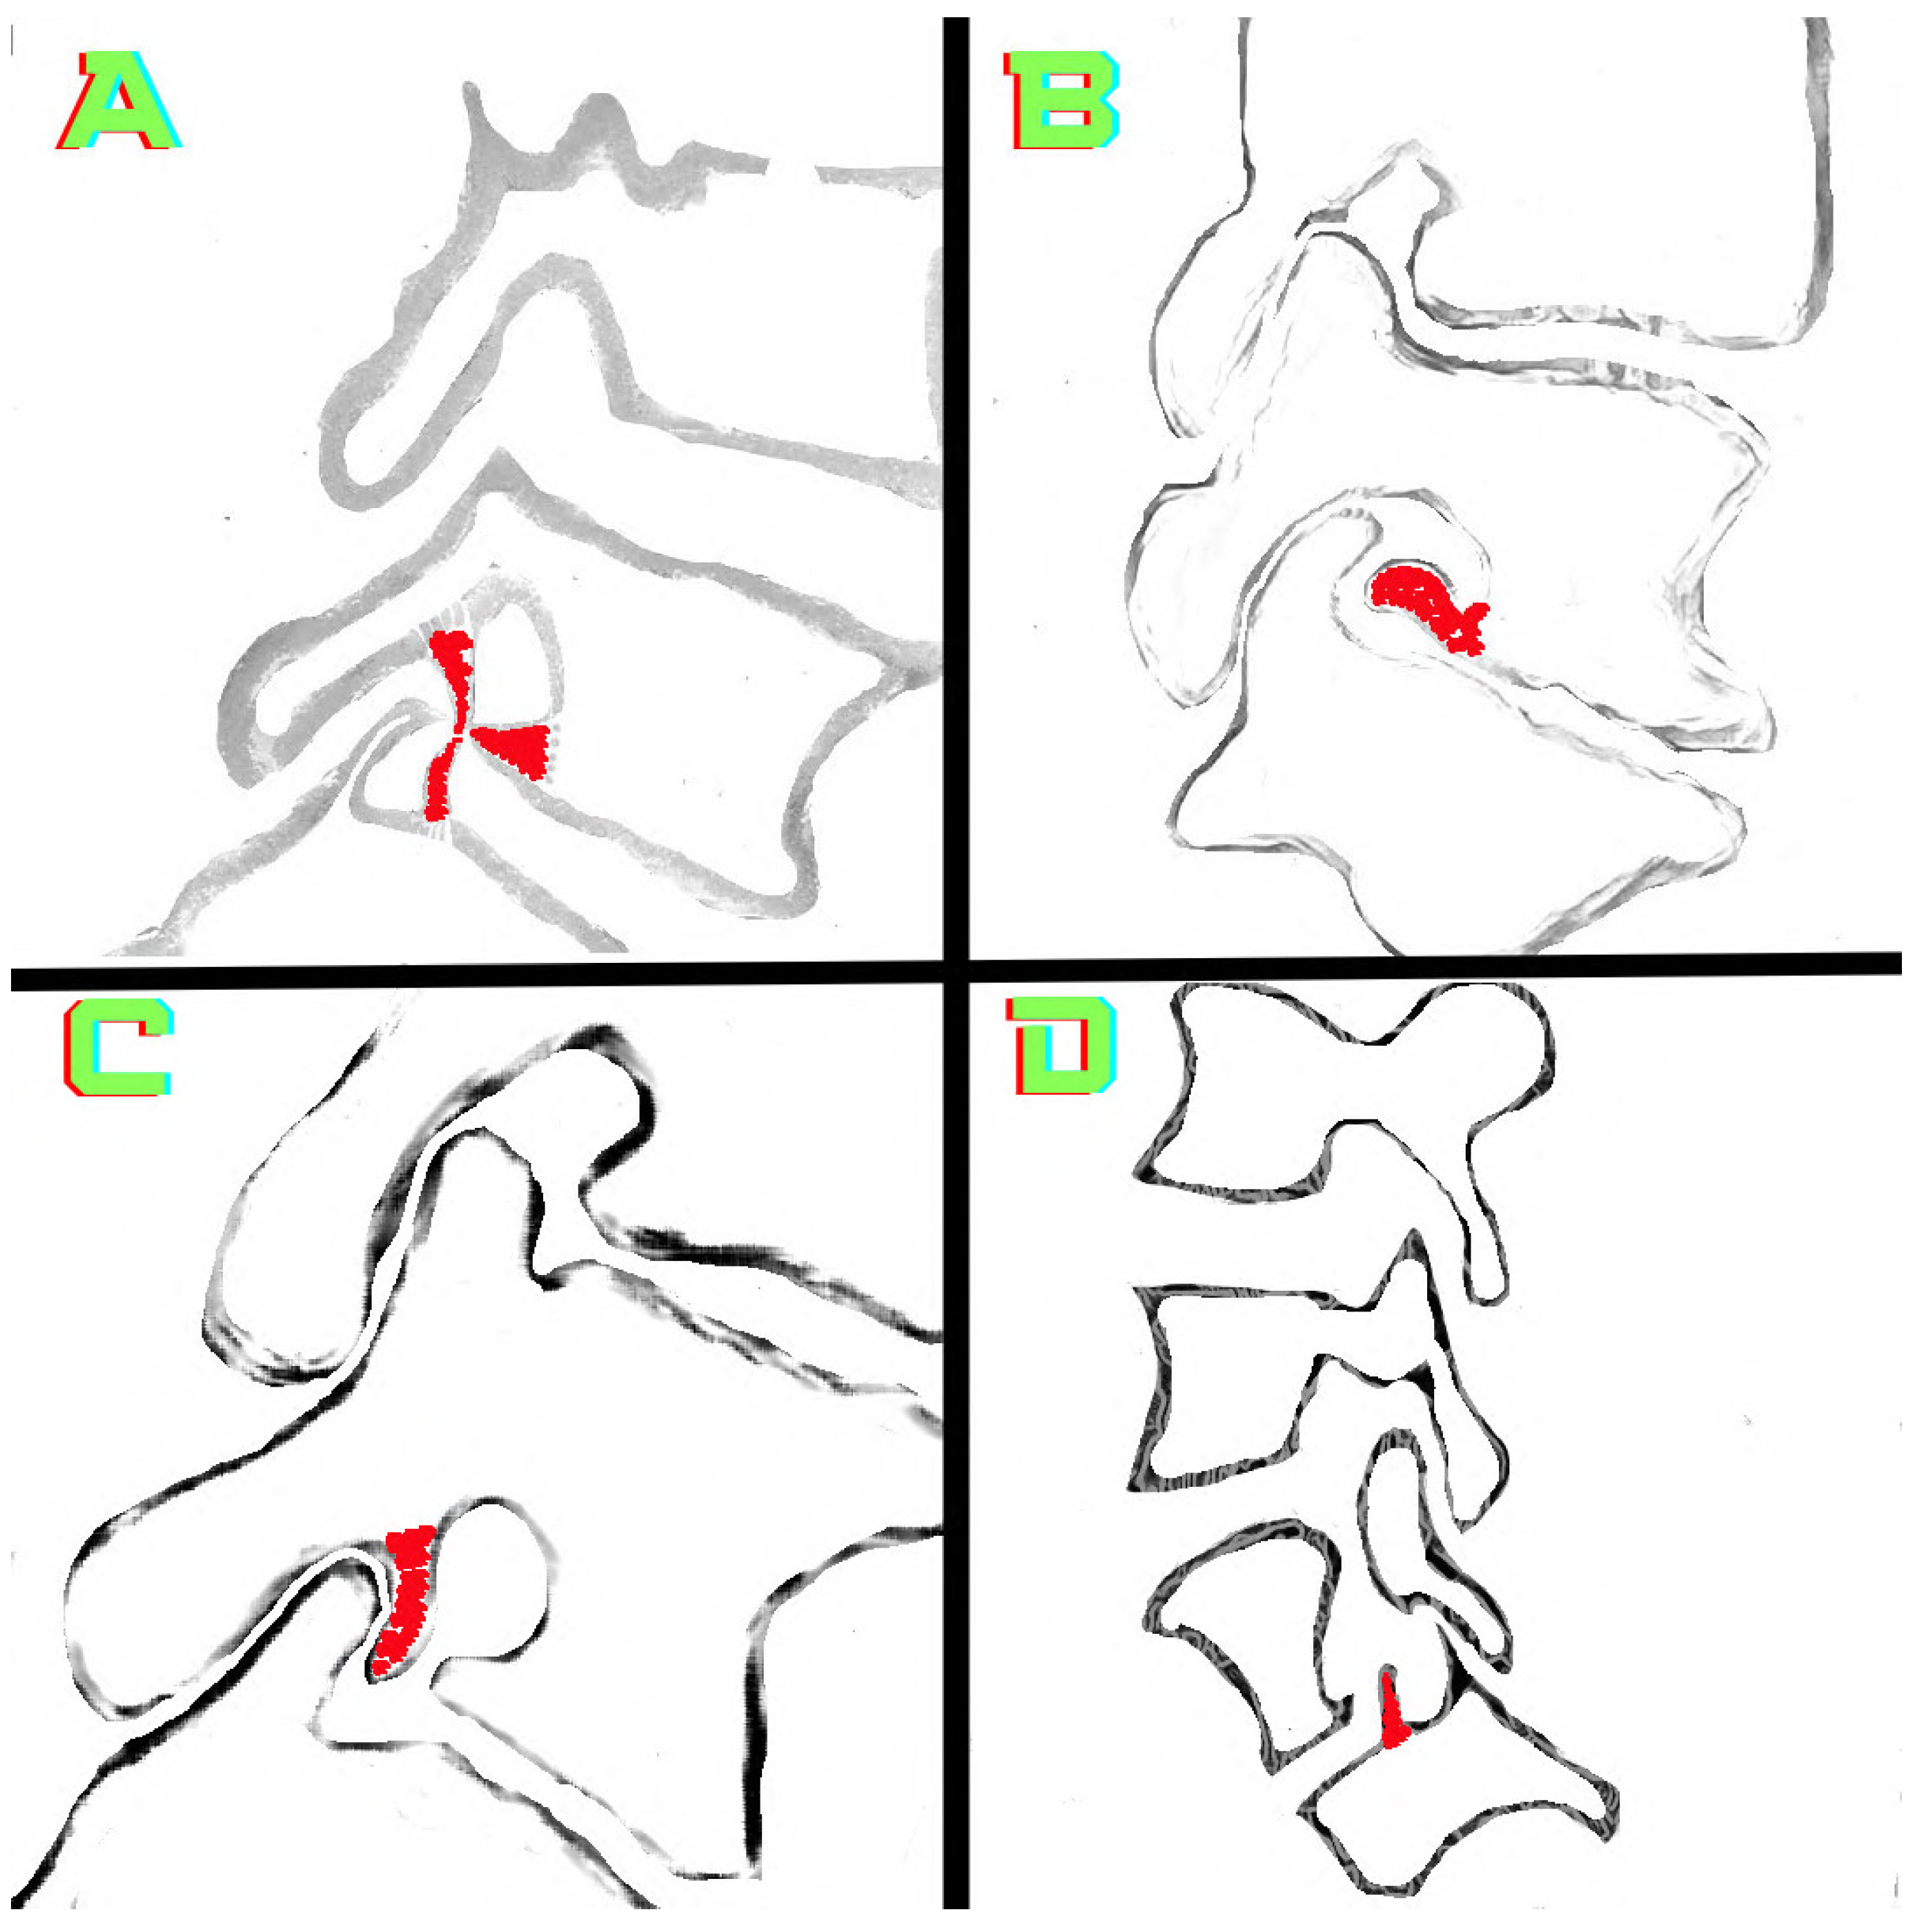

2.3. Image Analysis and Research Methods

3. Results

4. Discussion